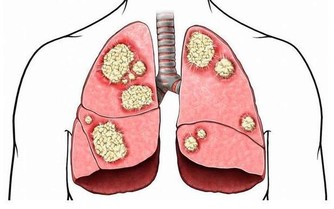

脾虛是中醫的說法,而中醫的脾也絕非僅是我們的脾臟,而是一個統管身體運化的系統,按照五行看,脾屬於土,位於中,也是身體很重要的部分。

一、脾虛的症狀